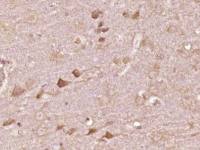

| 产品图片 |  Sample: MDA-MB-231(Human) Cell Lysate at 40 ug Primary: Anti-PALB2 (bs-0588R) at 1/300 dilution Secondary: IRDye800CW Goat Anti-Rabbit IgG at 1/20000 dilution Predicted band size: 131 kD Observed band size: 131 kD  Sample: HepG2(Human) Cell Lysate at 40 ug Primary: Anti-PALB2 (bs-0588R) at 1/300 dilution Secondary: IRDye800CW Goat Anti-Rabbit IgG at 1/20000 dilution Predicted band size: 131 kD Observed band size: 131 kD  Independently Validated Antibody, image provided by Science Direct, badge number 029682:Formalin-fixed and paraffin embedded pig skeletal muscle labeled with Rabbit Anti-PALB2 Polyclonal Antibody, Unconjugated (bs-0588R) at 1:100 for one hour at room temperature followed by conjugation to the secondary antibody Mach2 rabbit HRP-Polymer for 30 min at room temperature and DAB staining.  Independently Validated Antibody, image provided by Science Direct, badge number 029682:Formalin-fixed and paraffin embedded human breast cancer labeled with Rabbit Anti-PALB2 Polyclonal Antibody, Unconjugated (bs-0588R) at 1:100 from one hour at room temperature followed by conjugation to the secondary antibody Mach2 rabbit HRP-Polymer for 30 minutes at room temperature. Positive Control, the staining is correct.  Tissue/cell: human breast carcinoma; 4% Paraformaldehyde-fixed and paraffin-embedded; Antigen retrieval: citrate buffer ( 0.01M, pH 6.0 ), Boiling bathing for 15min; Block endogenous peroxidase by 3% Hydrogen peroxide for 30min; Blocking buffer (normal goat serum,C-0005) at 37℃ for 20 min; Incubation: Anti-PALB2 Polyclonal Antibody, Unconjugated(bs-0588R) 1:200, overnight at 4°C, followed by conjugation to the secondary antibody(SP-0023) and DAB(C-0010) staining  Blank control: Hela(blue), the cells were fixed with 2% paraformaldehyde (10 min) and then permeabilized with ice-cold 90% methanol for 30 min on ice.. Isotype Control Antibody: Rabbit IgG(orange) ; Secondary Antibody: Goat anti-rabbit IgG-FITC(white blue), Dilution: 1:100 in 1 X PBS containing 0.5% BSA ; Primary Antibody Dilution: 1μg in 100 μL1X PBS containing 0.5% BSA(green). |